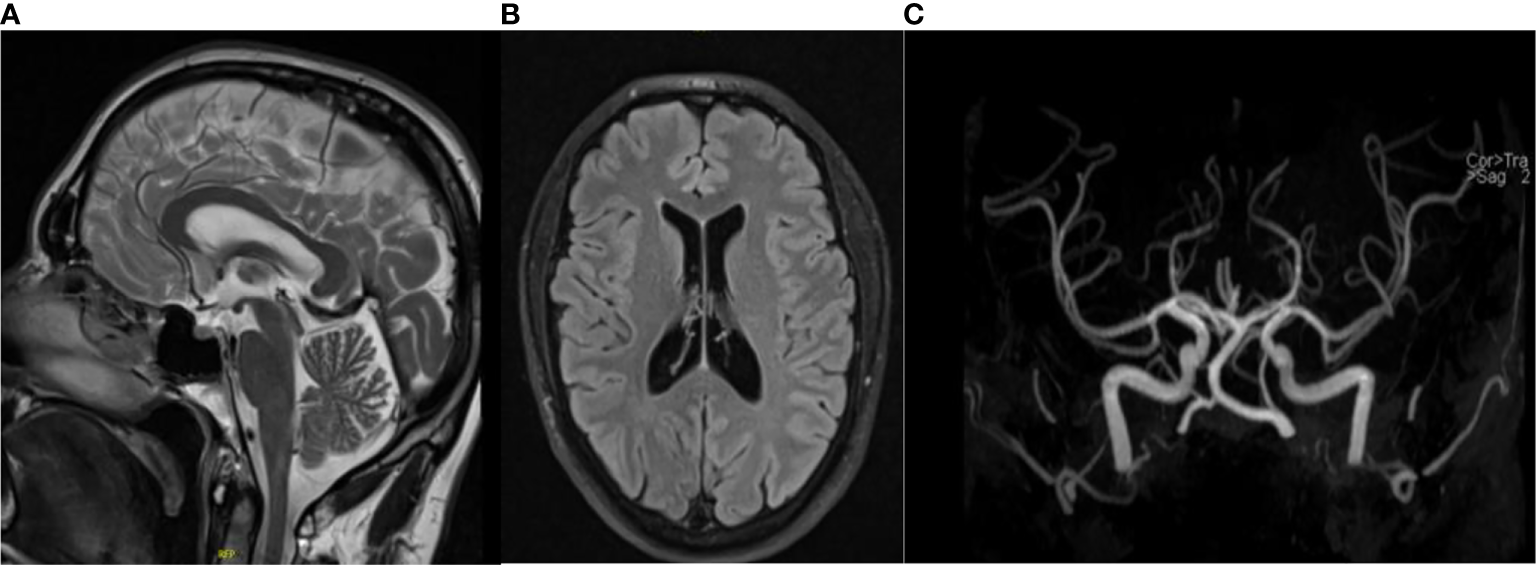

Postoperatively, the patient complained of right facial paresthesia as well as inguinal pain and hypoesthesia of the ventral side of the right limb and, to a less extent, on the left limb. Neurologic examination could not identify any deficits. Cerebral MRI excluded acute events such as hemorrhage or stroke (Figure 3). Completeness of resection was confirmed by normalized results of plasma normetanephrine (84 pg/ml) at 1-month follow-up after surgery. Next-generation sequencing revealed no mutations in over 20 known tumor susceptibility genes, either at the somatic or germline level, including the most prominent genes such as SDHX, RET, and VHL. Postsurgical normalization of plasma normetanephrine, together with the absence of genetic mutation as well as a PASS of 0, led to no further suspicion of metastatic disease. The profuse sweating as well as the dizziness was resolved within the next 6 months after the right adrenalectomy, while the pain, hypoesthesia, and headaches remained. The patient still complained of fatigue, headaches, and loss of concentration within the next months after adrenalectomy but to a more reduced degree than previously experienced. Further neurologic examination showed again no abnormalities aside from hypoesthesia of the ventral side of the right lower limb. The lumbar MRI showed broad-based subligamentous disc protrusion L5–S1 and a slight compression of the sciatic nerve. The inguinal pain was more severe when walking, suggesting degenerative changes in the sacroiliac joint. In the pelvic MRI, there was evidence of a rheumatic inflammatory genesis with slight edema ventrocaudal at the sacroiliac joint.

Figure 3

Magnetic resonance imaging depicting T2 flair (A) and coronal (B) and TOF angiography (C) views of the brain, excluding cerebral hemorrhages and stroke.